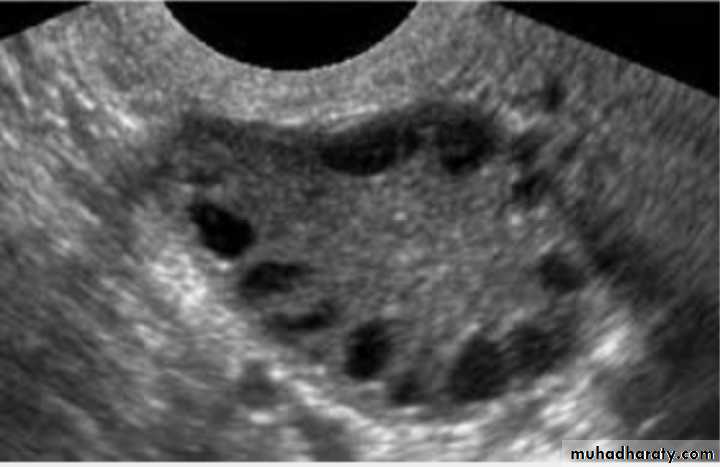

Dx: simple ovarian cyst

Description: round regular; smooth outline ;single echogenicity ;not contain blood ,contain only fluid

Tx:

-small and asymptomatic : conservative tx ;COCP

-large and symptomatic: surgical removal of cyst